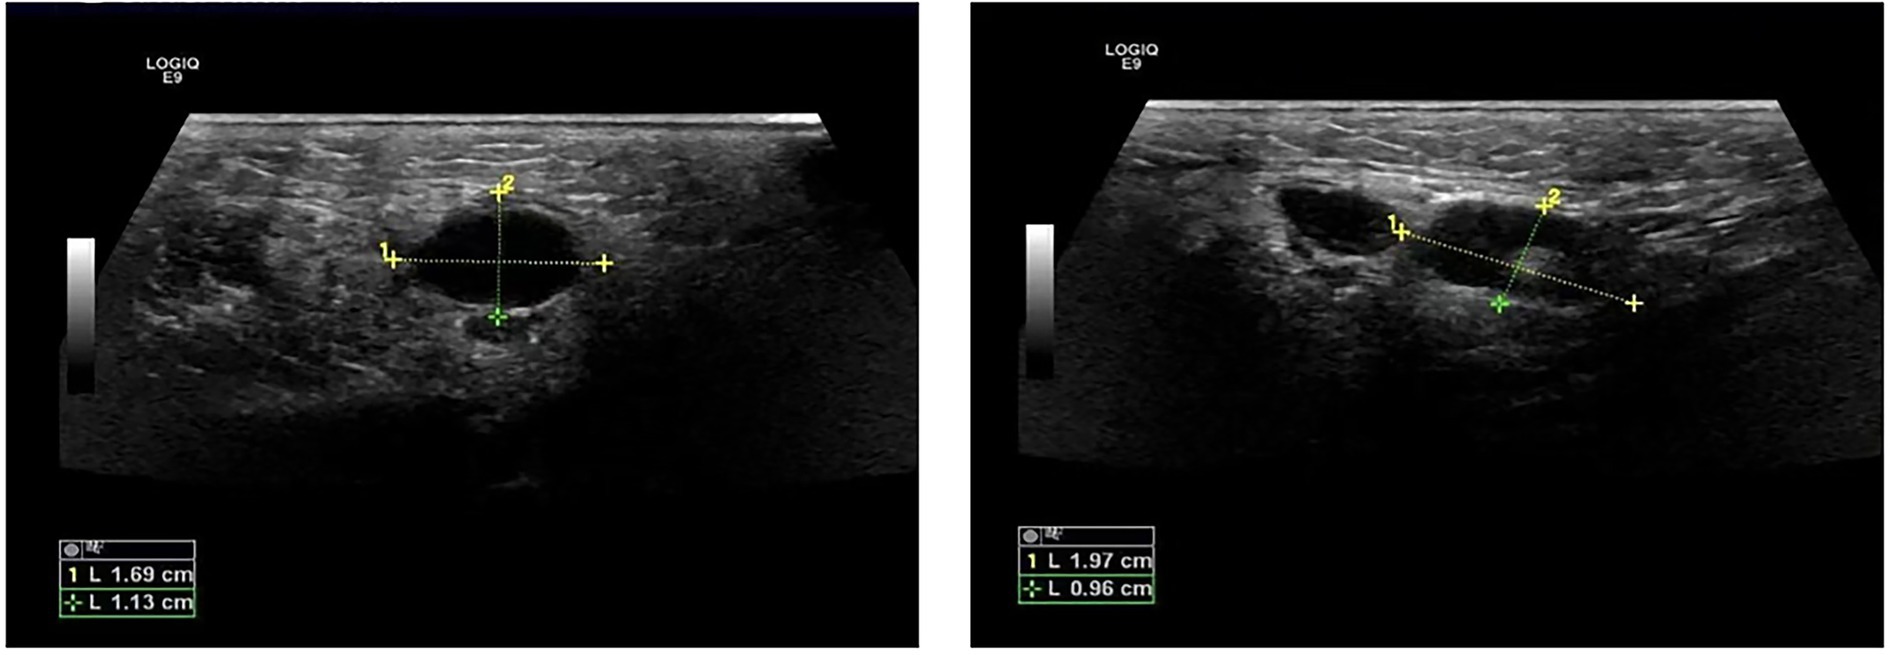

The patient was a 47-year-old female with a right maxillofacial abscess accompanied by distension and pain for 14 days. On November 22, 2024, the patient visited the local hospital’s Department of stomatology and was initially diagnosed with submandibular space infection. After local puncture and pus drainage, intravenous infusion of drugs such as clindamycin hydrochloride, levofloxacin and metronidazole for 3 days, the local symptoms worsened. On November 25, 2024, the patient visited the Oral and maxillofacial surgery outpatient Department of our hospital. The blood routine test did not show a positive result. The ultrasound examination indicated that a hypoechoic mass could be seen in the superficial part of the right masseter muscle of the patient, approximately 1.7*1.1 cm in size, with a clear boundary, regular shape, and uniform internal echo. No obvious blood flow signal was observed within it. Multiple lymph nod-like echoes could be seen in the right submandibular gland area, approximately 2.0*1.0 cm in size, with a clear structure and no obvious blood flow signal. Specialized physical examination indicated that the swelling range in the right submandibular area was approximately 2.0*1.5 cm (as shown in Figure 1), with local skin redness and swelling, elevated local skin temperature, tenderness (+), local fluctuation sensation, and slightly limited occlusal function. The re-diagnosis was submandibular space infection. Intravenous infusion of clindamycin, levofloxacin, ornidazole and other drugs for 3 days, but the therapeutic effect was not good. On November 29, 2024, the patient was referred to the Department of Infectious Diseases of our hospital. Based on her long-term epidemiological history of contact (including feeding and delivering) with livestock such as cattle and sheep, brucellosis is highly suspected. The suspension was sent to Jilin Jinyu Medical Laboratory for sequencing of the next generation of the metagenome (mNGS) the results showed that the relative abundance of Brucella with sequence number of 9133191 was 99.97%, and the coverage of Brucella suis with sequence number of 8525228 was 98.94%. Supplementary Brucella test tube agglutination method test suggests Brucella test tube agglutination 1:200++++. The blood culture and drug sensitivity tests were completed, indicating that the pathogenic bacterium was Brucella. Combined with the epidemiological history, metagenomic next-generation sequencing (mNGS) (as shown in Figure 2) and other auxiliary examination results, the diagnosis was modified to brucellosis. Surgical dressing changes were performed daily, and intravenous infusion of doxycycline 0.1 g q12h and rifamycin 0.5 g q12h was carried out. After 6 days of anti-brucellosis treatment, the patient’s symptoms were relieved and the patient was discharged. Blood cultures were negative at the first, third and sixth month after discharge (see Table 1).

Figure 1

Ultrasound images of abscess.